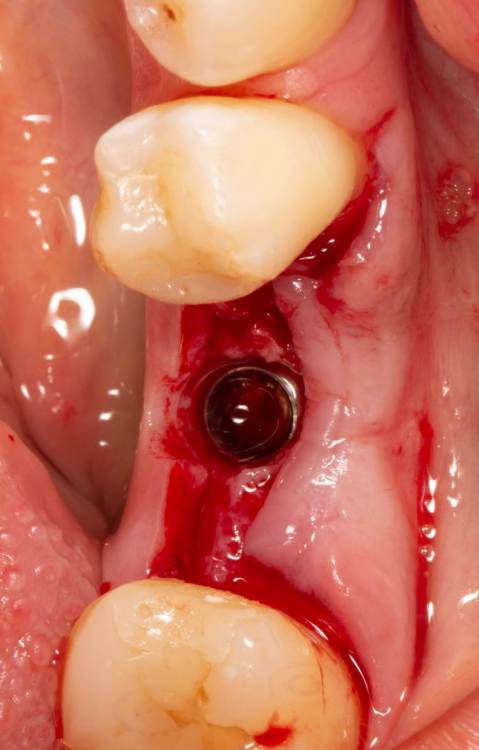

Женька Опубликовано 19 июня, 2023 Поделиться Опубликовано 19 июня, 2023 Здравствуйте, коллеги. Примерно с нового года начал ставить ТЛ имплантаты Дентиум. Что-то под заглушку (не поймал торки, представляете?). Что-то на низких формирвателях. И вот пришла пора протезирования, но отпустить к ортопеду не подготовив десну - не получается. Создал сам себе проблем, сегодня вот исправлял. Получилось неплохо? 3 Ссылка на комментарий

TIGER Опубликовано 20 июня, 2023 Поделиться Опубликовано 20 июня, 2023 Это ж не TL,cубкрестально же.А так я бы длиннее брал ССТ,с захватом соседей Ссылка на комментарий

Женька Опубликовано 20 июня, 2023 Автор Поделиться Опубликовано 20 июня, 2023 @TIGER в смысле это не ТЛ?))) Фото с редукцией не сделал. А то что, шейку погружал - так нужно было. Но это ТЛ. Поверьте) я был на имплантации) Ссылка на комментарий

АнтонТЛТ Опубликовано 20 июня, 2023 Поделиться Опубликовано 20 июня, 2023 Думаю имеется ввиду что имплантат TL установлен по протоколу BL Ссылка на комментарий

Женька Опубликовано 20 июня, 2023 Автор Поделиться Опубликовано 20 июня, 2023 @АнтонТЛТ мы же позиционируем платформу относительно зенита? Есть ли разница тогда, какой имплантат мы выбираем? Вообще весь смысл здесь был заложен в том, что толщина гребня была не очень. Хотелось поставить тонкий имплантат 3.6. Но рисковать тонкой платформой не хотелось, поэтому выбор пал на 4.8 платформу ТЛ и тело имплантата 3.6 1 Ссылка на комментарий